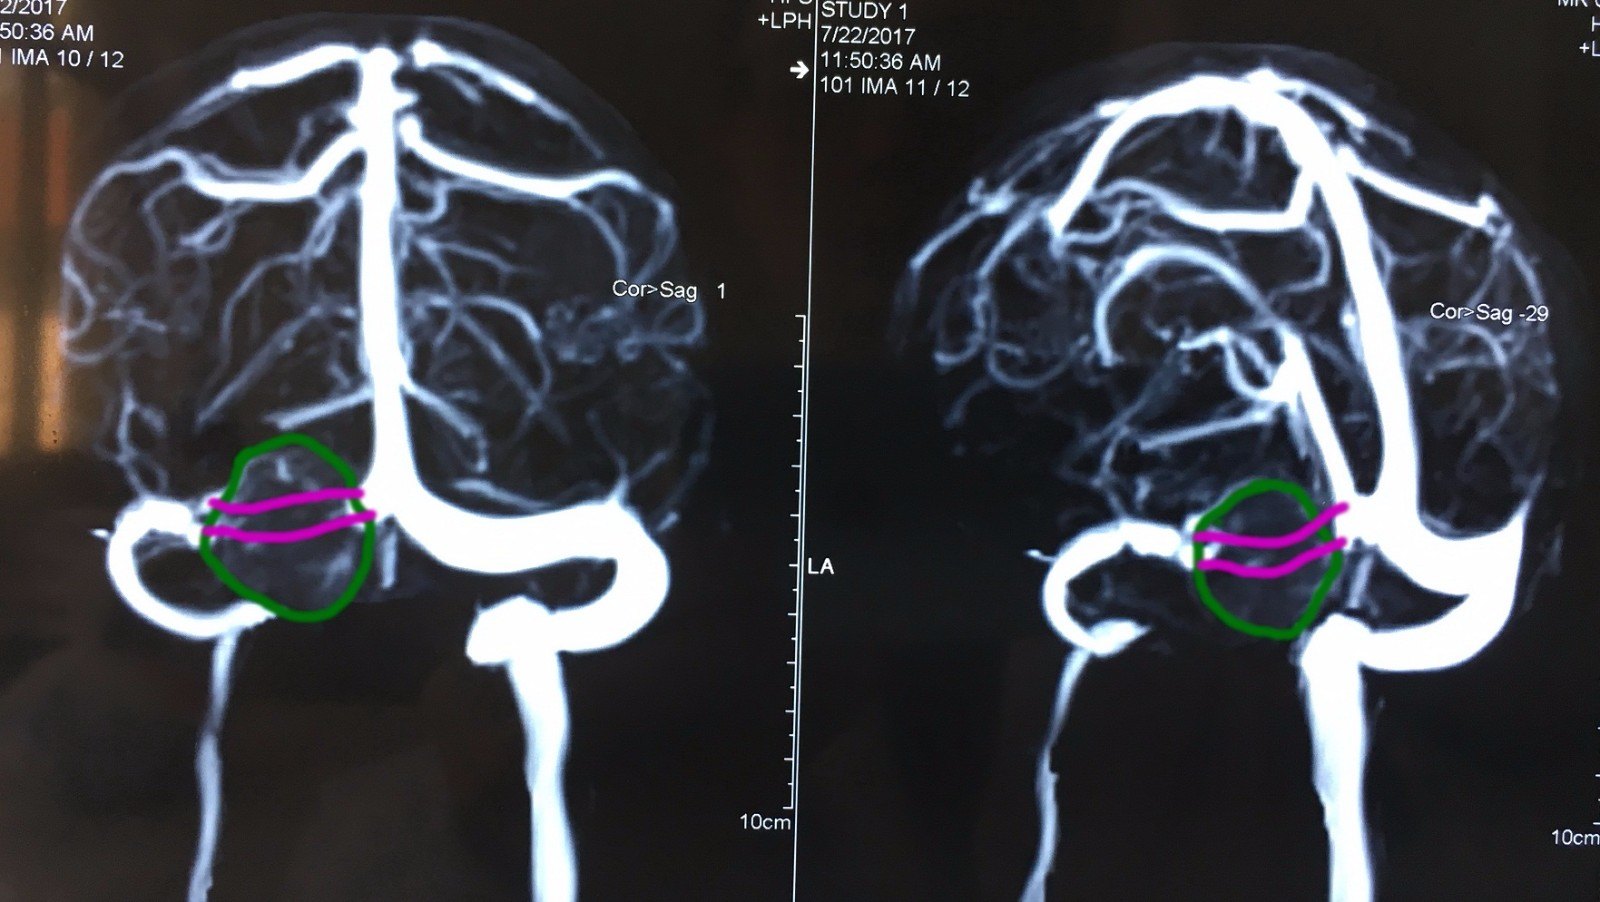

一例横窦,乙状窦血栓形成与静脉窦解剖变异的鉴别

图片尺寸1138x1301